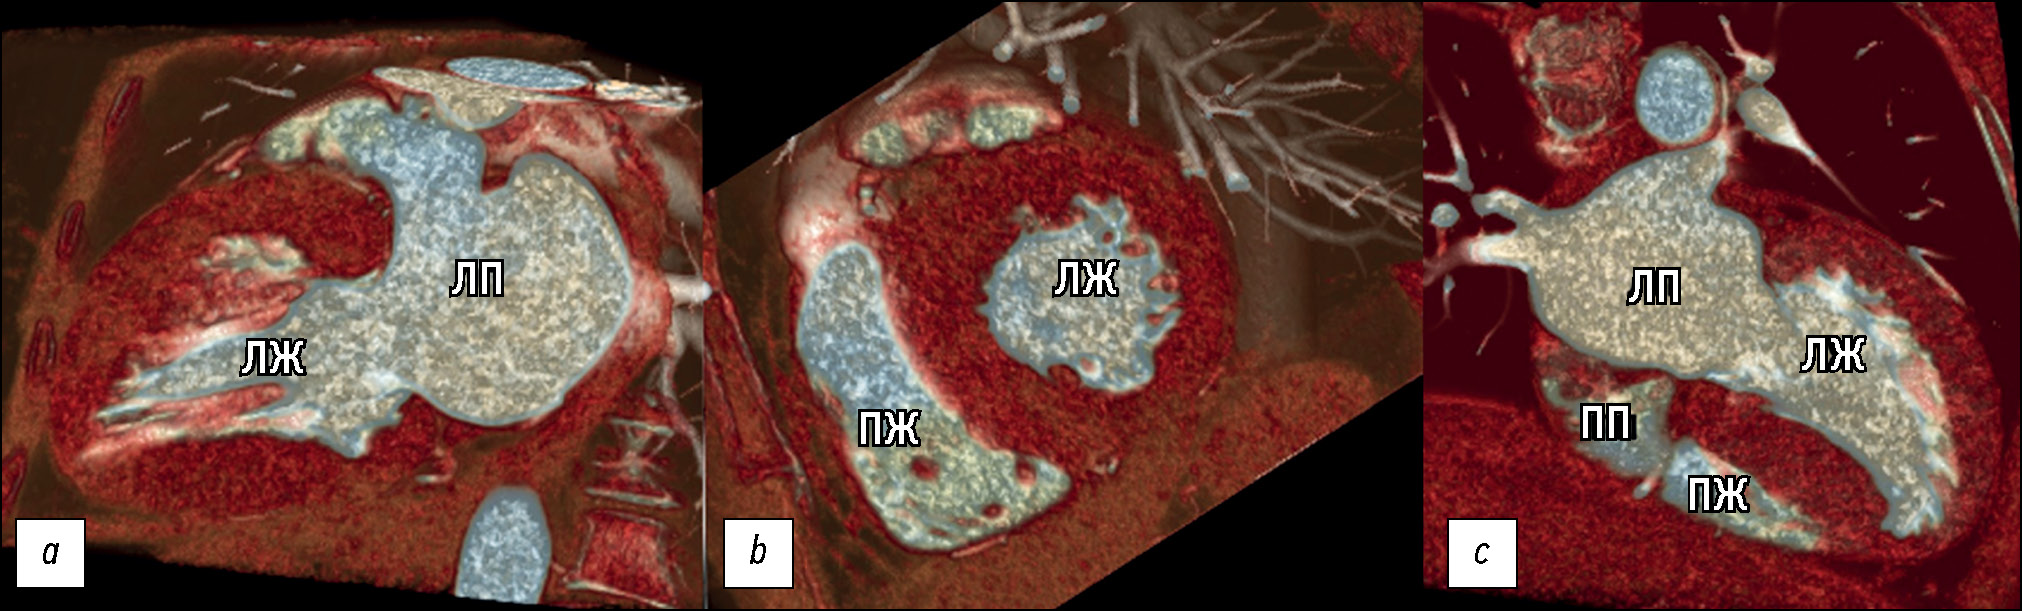

Согласно локализации гипертрофии миокарда ЛЖ по данным КТ были сформированы морфологические варианты ГКМП. Наше исследование демонстрирует вариабельность фенотипических проявлений ГКМП, условно разделённых на 5 морфологических типов и не ограниченных данными вариантами. Большинство — 26 из 47 (55%) — пациентов в нашей работе имели диффузно-септальный морфологический фенотип ГКМП (рис. 4).

Рис. 4. Пример 3D-изображений компьютерной томографии диффузно-септального фенотипа ГКМП: a — плоскость двухкамерной проекции левых отделов сердца; b — короткая ось сердца; c — четырёхкамерная проекция сердца. ЛЖ — левый желудочек, ЛП — левое предсердие, ПЖ — правый желудочек, ПП — правое предсердие.

Среднежелудочковый фенотип выявлен у 5 из 47 (11%) пациентов (рис. 5), из них среднежелудочковый фенотип с апикальным выпячиванием/аневризмой ЛЖ выявлен у 2 (40%) пациентов.

Рис. 5. Пример MPR и 3D-изображений компьютерной томографии среднежелудочкового фенотипа гипертрофической кардиомиопатии с признаками систолической обструкции полости ввиду вариантной аномалии хордо-папиллярного аппарата и асимметричной гипертрофии миокарда левого желудочка: a — плоскость двухкамерной проекции левых отделов сердца; b — трёхкамерная проекция сердца; c — четырёхкамерная проекция сердца. Апикальное смещение заднебоковой папиллярной мышцы и прямой контакт с передней створкой митрального клапана; расщепление ножек сосочковых мышц + добавочная мышечная трабекула.

У 8 из 47 (18%) пациентов был выявлен ассиметричный вариант фокально-базального фенотипа ГКМП с S-образной/«сигмовидной» МЖП, характеризующийся гипертрофией миокарда перегородочных сегментов на базальном уровне вблизи ВОЛЖ (рис. 6).

Рис. 6. Пример 3D-изображений компьютерной томографии фокально-базального фенотипа гипертрофической кардиомиопатии: a — плоскость двухкамерной проекции левых отделов сердца; b — короткая ось сердца. ЛЖ — левый желудочек; ЛП — левое предсердие; ПЖ — правый желудочек; МЖП — межжелудочковая перегородка; Ао — аорта.

У 4 из 47 (8%) пациентов выявлен концентрический фенотип, характеризующийся симметричной гипертрофией стенок ЛЖ с уменьшением полости. Еще 4 (8%) пациента соответствовали апикальному фенотипу (рис. 7).

Рис. 7. Пример MPR и 3D-изображений компьютерной томографии пациента с апикальным фенотипом гипертрофической кардио-миопатии после имплантации кардиовертер-дефибриллятора: a — плоскость четырёхкамерной проекции; b — двухкамерная проекция левых отделов сердца; c — 3D VRT реконструкции четырёхкамерной проекции сердца.